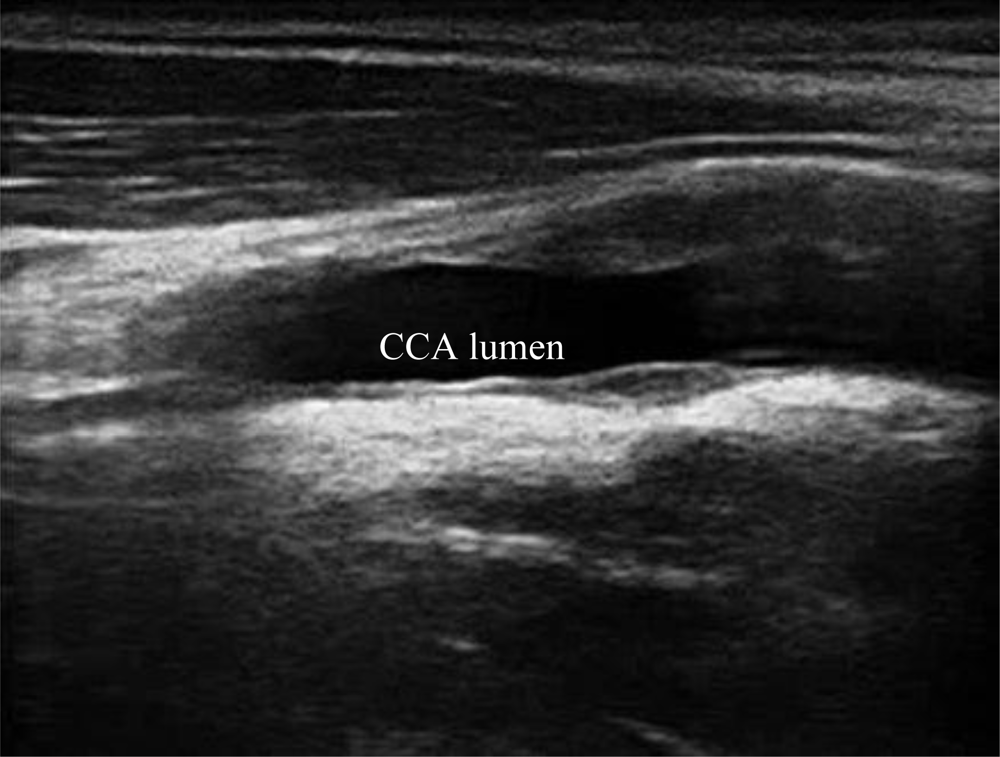

A typical B-mode image is shown in Figure 1. There are plaques on both near and far walls. On the contrary, a typical CCA image without plaque having thin and thick IMT is shown in Figures 2 and 3, respectively. Outlining the boundaries of intima and adventitia is not easy, especially on the near wall. Some features have been studied in previous studies [7,11], in which the most frequently used feature is the gradient of gray-values. From our previous studies [7,14,17], it is found that MacLeod operator combined with some specific enhancement filters are very suitable for feature extraction in intima and adventitia detections.

We have tested three image sequences: S1, S2, and S3, they include plaques, thin, and thick IMT, respectively. All sequences have at least three heart cycles. Figures 6 to 8 show the test results of IMT detection on the far wall, whereas Figures 9 to 11 show the test results of IMT detection on the near wall of the three sequences.

In Figure 6 there is a plaque on the right-hand side which is successfully detected. A total of 78 images are in sequence S1. Another example shows the ability to detect a thin IMT as shown in Figure 7. A total of 111 images are in sequence S2. Figure 8 shows the thick IMT test result. A total of 86 images are in sequence S3.

Figure 9 shows that our method has the ability to detect the plaque on the near wall. Figure 10(b) shows the problem using the method in [7] to detect the dual lines when the near wall is not clear. However, the proposed method can have a good result, as shown in Figure 10(c). As well, it produces good results in thicker IMT detection (Figure 11).